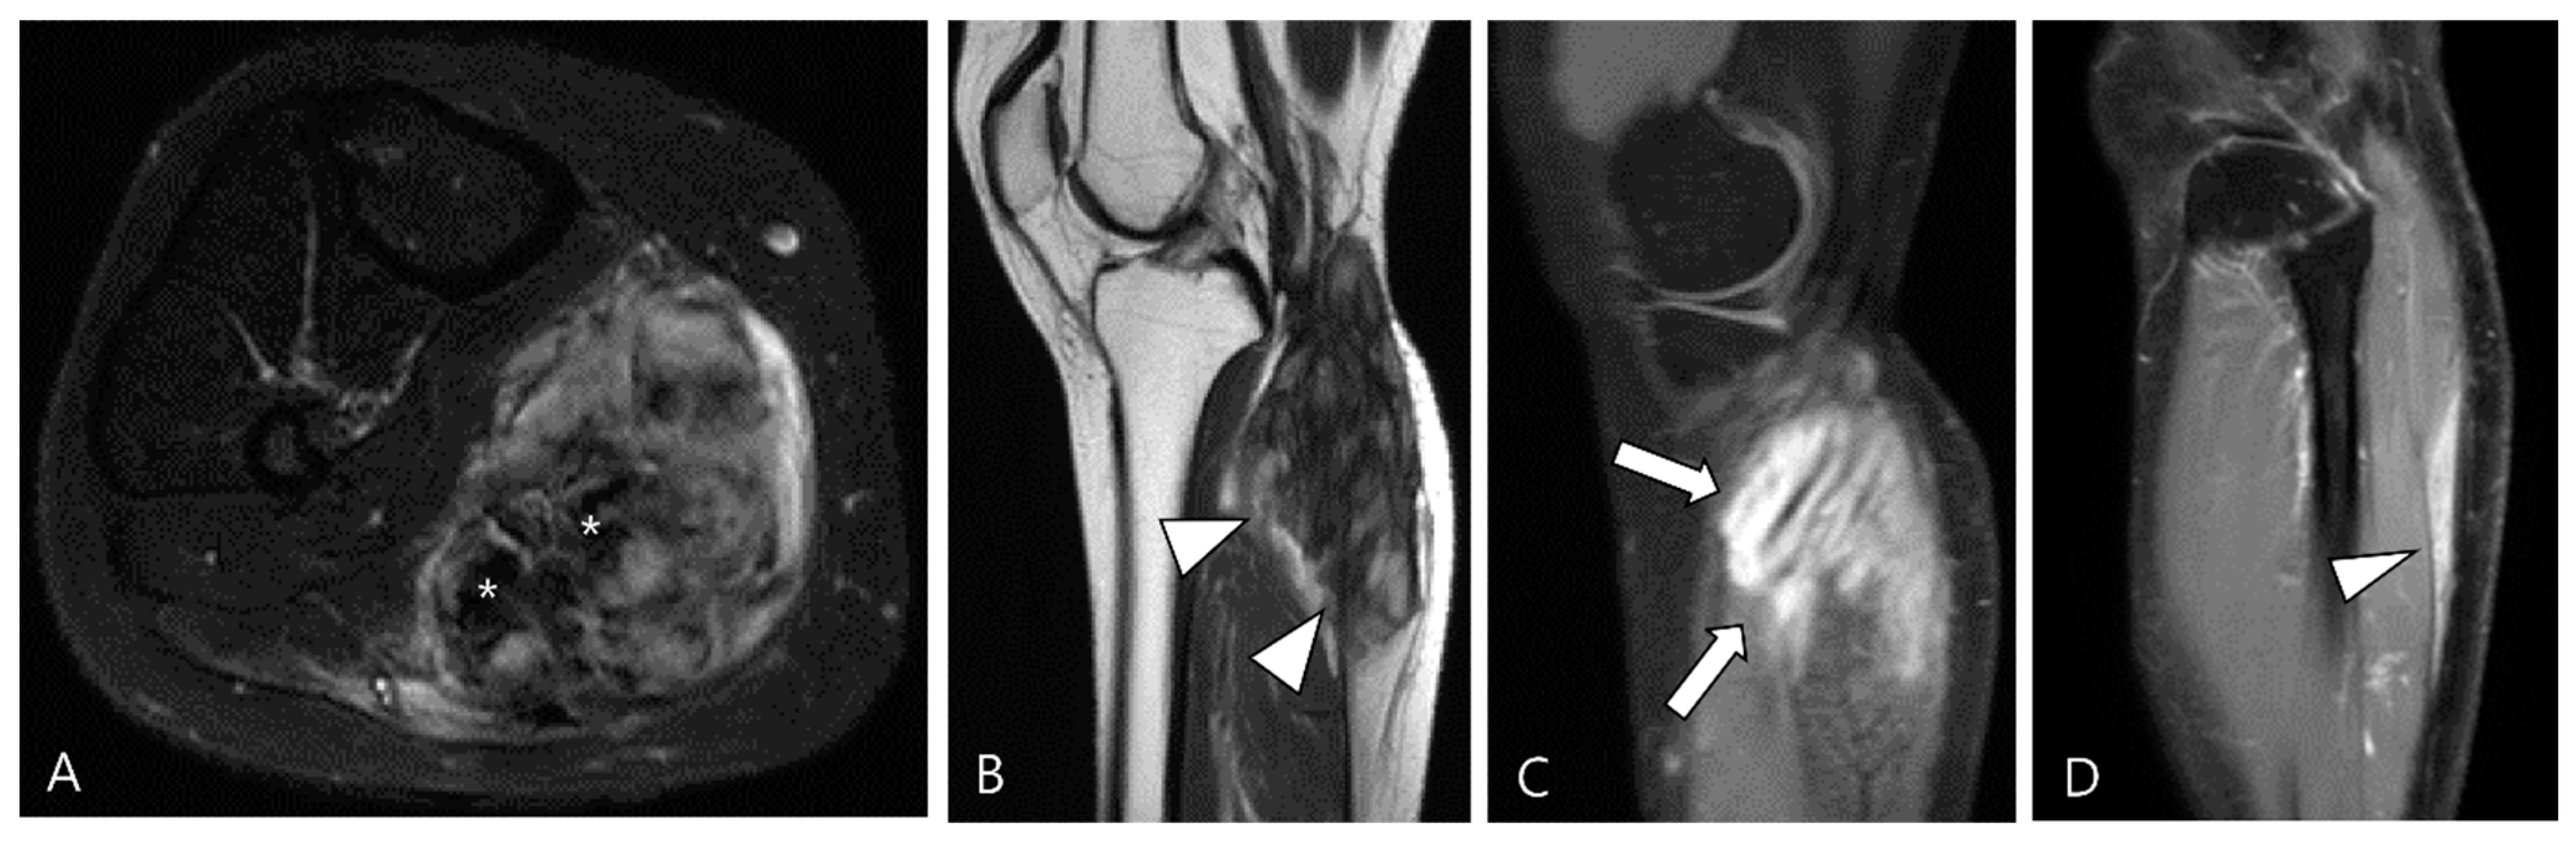

3.2.2. Extra-Abdominal Desmoid-Type Fibromatosis (DF)

DF is a locally aggressive (myo)fibroblastic neoplasm that originates in deep soft tissues, characterized by infiltrative growth and a propensity for local recurrence without metastatic potential [63,64]. Aggressive fibromatosis, musculoaponeurotic fibromatosis, and desmoid tumor are synonymous term for DF [63]. The major subgroups include superficial (palmar and plantar) and deep fibromatoses. The deep fibromatoses are further classified as extra-abdominal (found in the upper extremities, lower extremities, trunk, head and neck), abdominal wall (arising from musculoaponeurotic structures of the abdominal wall), and intra-abdominal (in the mesentery or pelvis) [63,65]. Extra-abdominal DF originates from the connective tissue of muscle and their overlying aponeurosis or fascia, potentially infiltrating adjacent subcutaneous tissue and muscle [65]. DF exhibits a heterogeneous appearance on MRI, with variable SI on T2WI and T1WI due to diverse intralesional components, including myxoid matrix, cellular stroma, and fibrous tissue/collagen bands [66,67]. Decreased T2 SI corresponds to dense collagen and hypocellularity, while increased T2 SI correlates with high cellularity [66]. TSGCT and extra-abdominal DF exhibit similar SI on MRI, but DF manifests along the fascial planes, with or without muscle invasion. Recognizing the characteristic signs of extra-abdominal DF aids in distinguishing between the two diseases (Figure 16); DF displays the staghorn sign (fingerlike tumor extension into muscle or subcutaneous fat) and fascial tail sign [68].

Figure 16.

A 40-year-old female with extra-abdominal DF in the lower leg. (A) Axial fat-suppressed T2WI shows a slightly hyperintense intramuscular mass with intralesional dark SI portions (asterisks) in the medial head of the gastrocnemius muscle. (B) Sagittal T2WI shows this lesion with a lobulated contour with an infiltrative margin (arrowheads). (C,D) Sagittal contrast-enhanced fat-suppressed T1WIs show that this mass displays heterogenous enhancement and finger-like tumor extension into adjacent muscle (termed as “staghorn sign”, arrows) and a tapering appearance of the tumor extension along the fascia (termed as “fascial tail sign”, arrowhead).